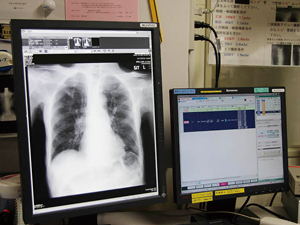

CALNEO Cは撮影から約1秒で画像が取得でき,

検査効率が向上

FCRからフィルムレスPACSへと,デジタルによる撮影,運用のシステムを構築してきた同院で,一般撮影部門のデジタル化の次のステップとして進められているのがFPD(DR)の導入である。同院の一般撮影室は,胸部2室,骨・腹部2室,乳房,歯科・小児,骨塩定量装置で構成されているが,2007年に骨・腹部撮影室に最初のDRとして「FUJIFILM DR BENEO DR-XD100(以下,BENEO)」が導入された。2011年には,2つの胸部撮影室に間接変換方式FPDを採用した立位撮影タイプの「CALNEO U」が,そして2013年3月に,骨・腹部のもう1部屋にBENEOを導入すると同時に,CRに代わりワイヤレスFPDである「FUJIFILM DR CALNEO C(以下CALNEO C)」の半切タイプ(1417 Wireless SQ),四ツ切タイプ(mini Wireless SQ)が採用された。

CALNEO Cは,ISS方式を採用した間接変換方式のワイヤレスタイプのFPDである。現在,同院では骨・腹部撮影室のBENEOとの組み合わせで使用されている。一般撮影を担当する盛満信広主任はワイヤレスFPDのメリットについて,「CRに比べて撮影時間が短縮されました。BENEOに比べても,表示までの時間は短くなっています。撮影後に読み取りの必要がありませんので,ポジショニングを微調整して連続した撮影が可能です。実際に撮影がスピーディになって,患者さんの待ち時間も短縮していることを実感しています」と言う。

CALNEO Cの撮影線量は,CRに比べて30〜50%少ない設定になっており,被ばく線量も低減されている。増渕技師長は,「画質の向上やそれに伴う被ばく線量の低減,撮影時間の短縮,検査のワークフローの向上などを考えると,ワイヤレスタイプのFPDは一般撮影系のひとつの完成形ではないかと思います」と評価する。